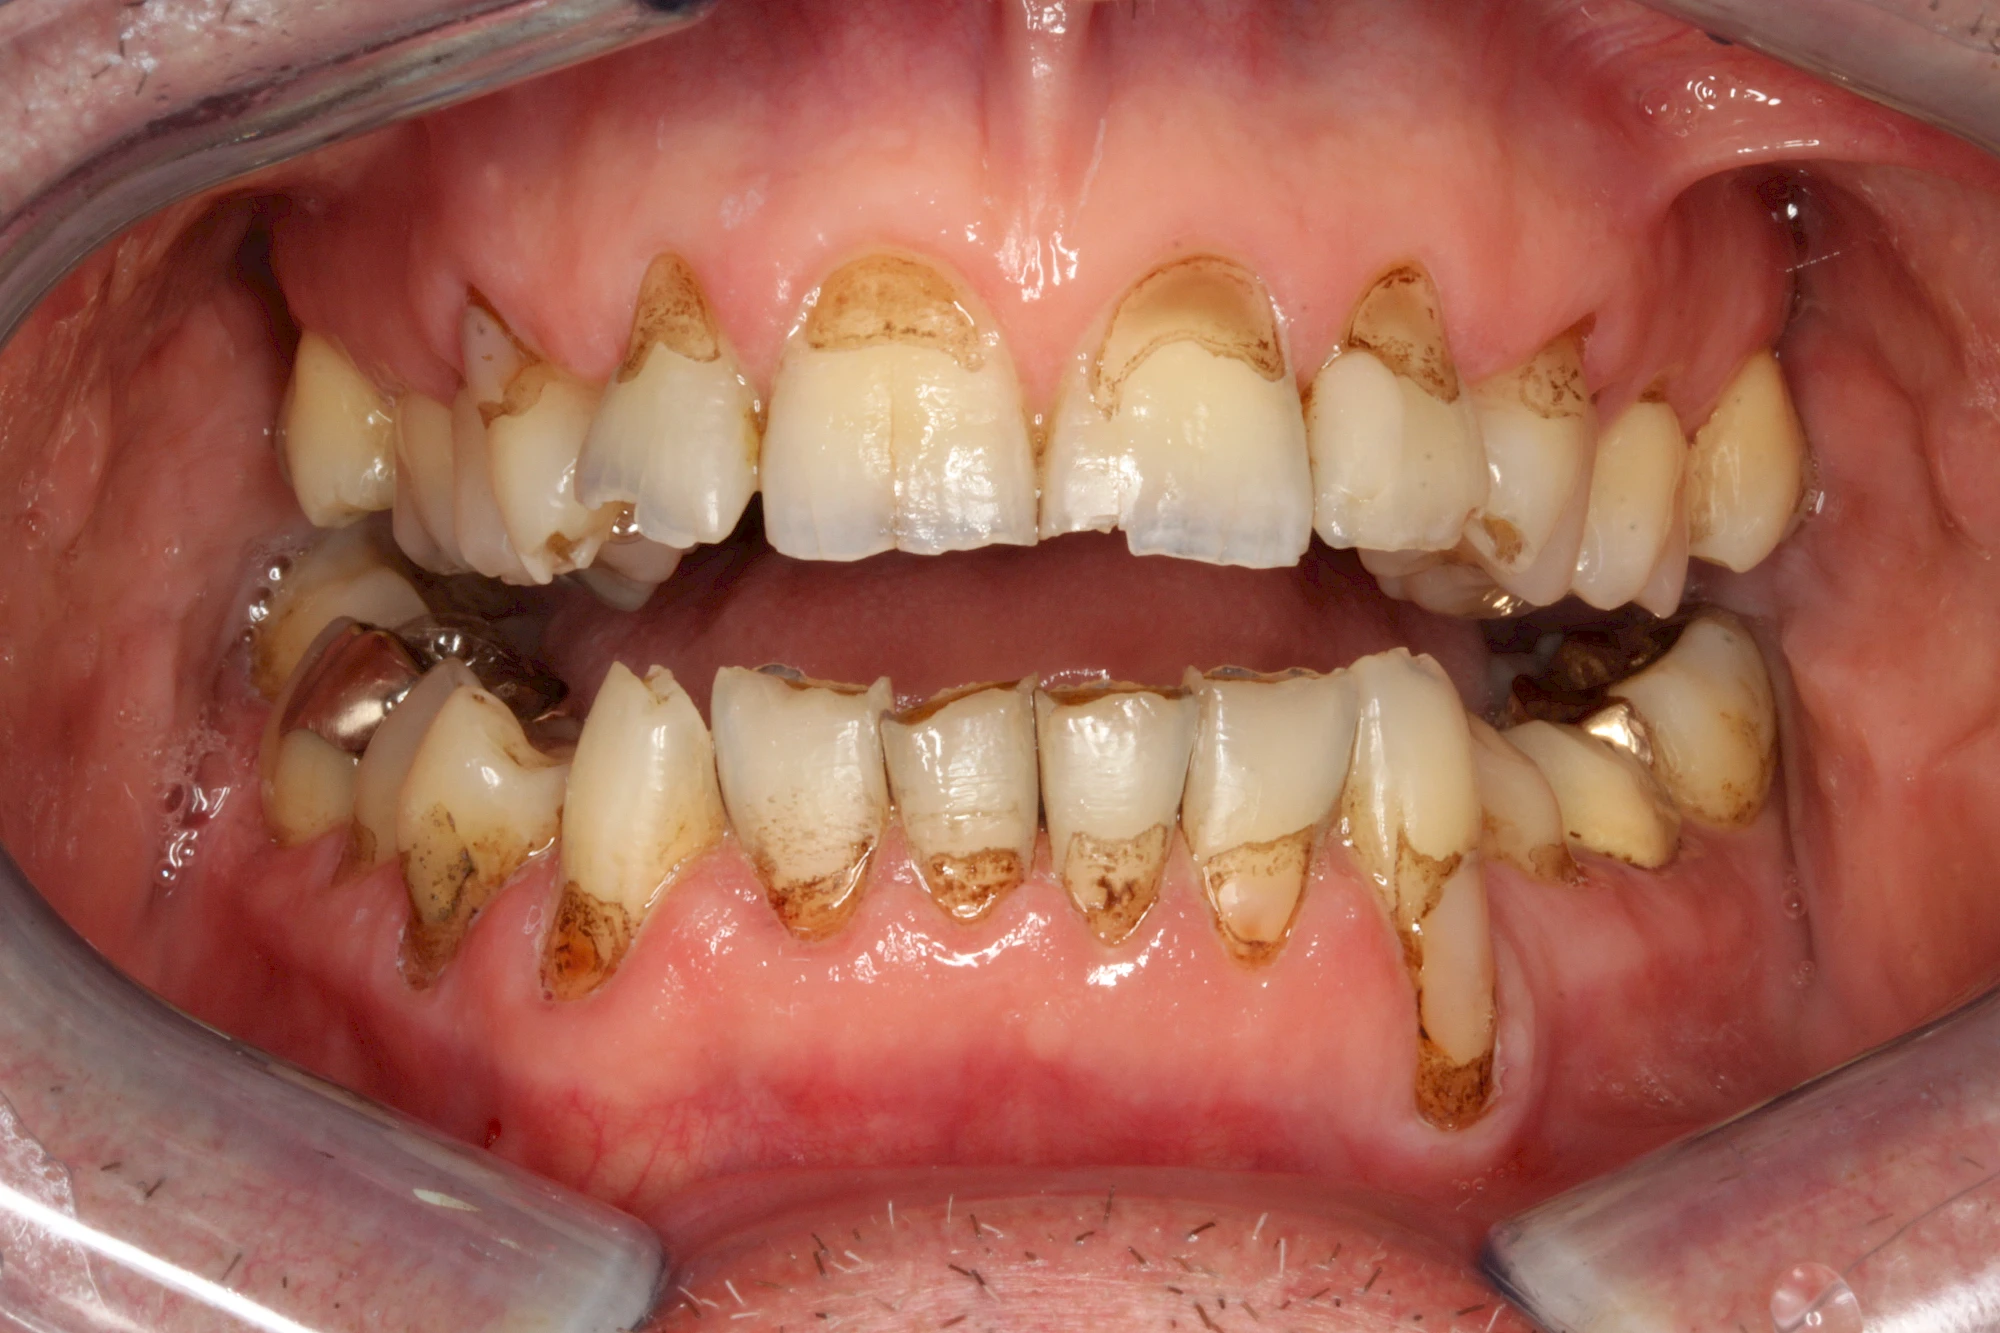

Von außen (exogen) eher dunkel gefärbt und meist mehrere Zähne betroffen:

- Genußmittel (Tee, Kaffee, Rauchen)

- Medikamente (z. B. Eisen)

Äußere Verfärbungen durch Genußmittel oder Medikamente (Eisen!) lassen sich meist nur durch den Zahnarzt z. B. mit einer professionellen Zahnreinigung entfernen.